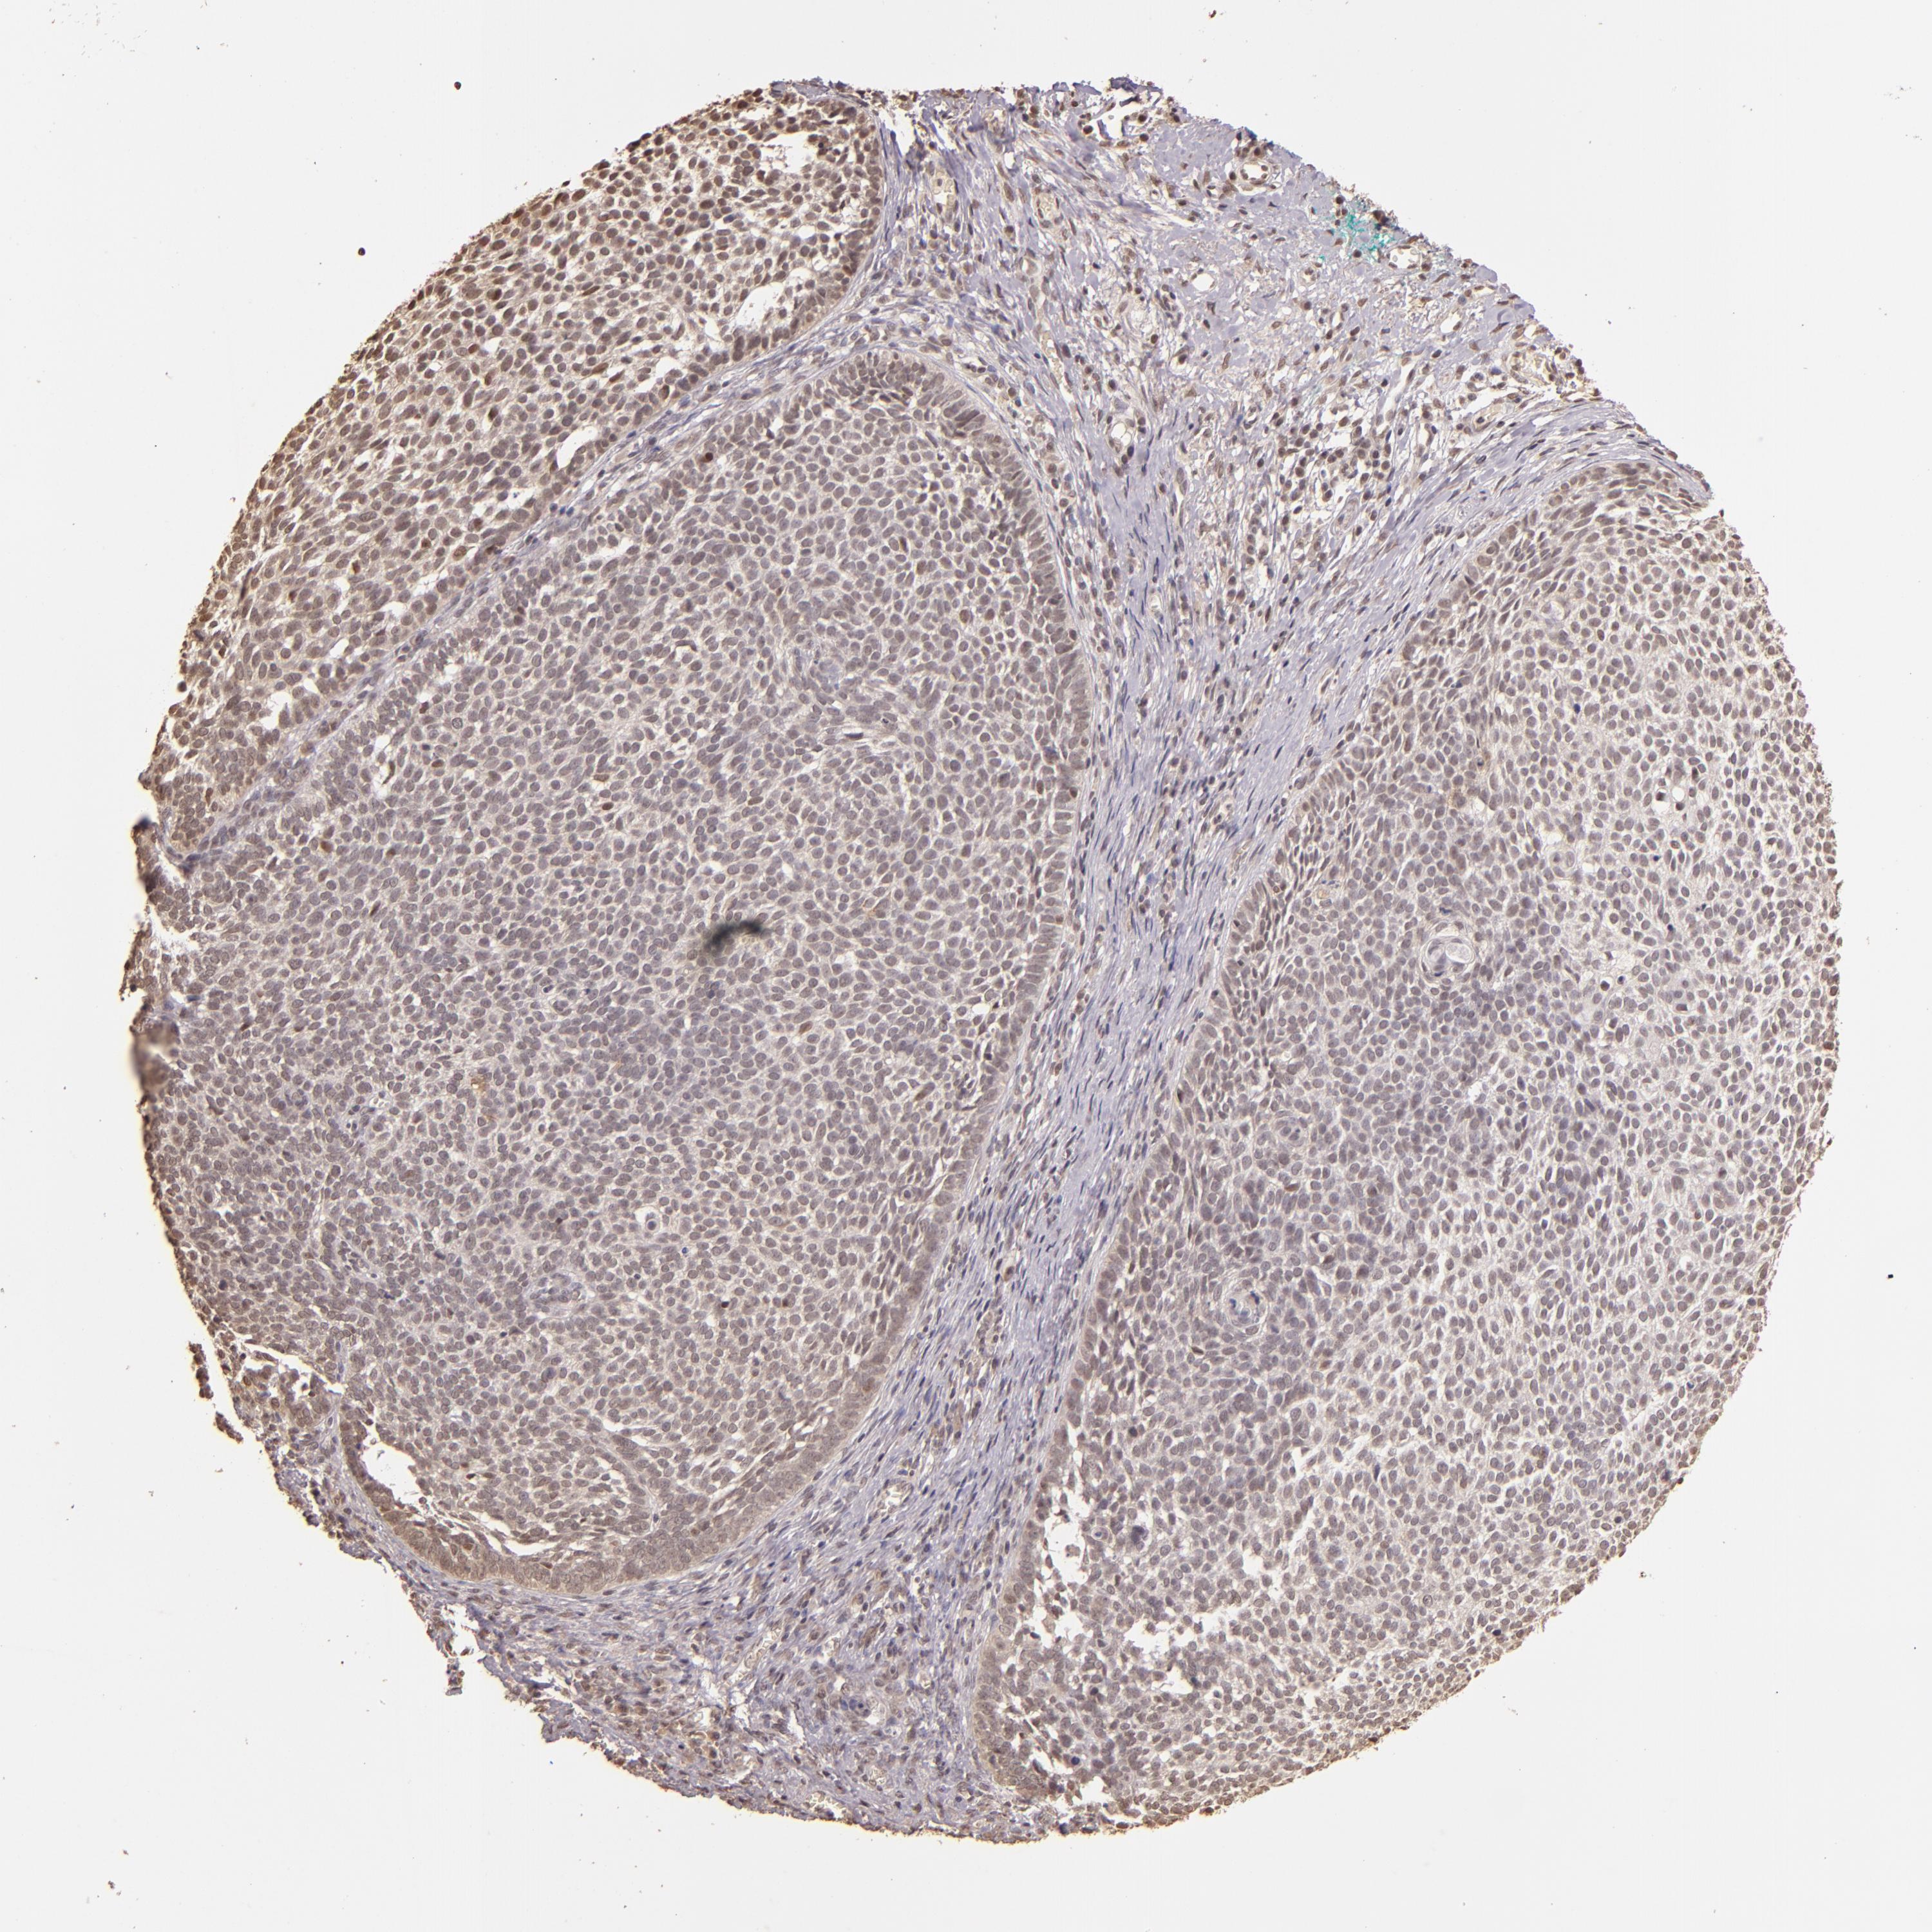

CANCER SKIN CANCER Show tissue menu

Basal cell and squamous cell cancer

SKIN CANCER - Protein expressioni

A mouse-over function shows sample information and annotation data. Click on an image to view it in a full screen mode. Samples can be filtered based on level of antibody staining by selecting one or several of the following categories: high, medium, low and not detected. The assay and annotation is described here.

Each image is clickable and will lead to virtual microscopy that enables deeper exploration of all samples and also displays staining intensity scores, fraction scores and subcellular localization as well as patient and tissue information for each sample.

Antibody CAB002676

Staining

High

Intensity

Strong

Quantity

>75%

Location

Nuclear

Squamous cell carcinoma, NOS

Basal cell carcinoma